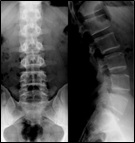

- Radiografía (Rayos X)

Es una prueba accesible, barata y no invasiva que puede realizarse en las fases iniciales de la enfermedad. Tiene como problema la radiación X utilizada. Sirve, especialmente, para valorar la disposición de los huesos y detectar fracturas, fisuras y desplazamientos óseos. Sirve también para observar indirectamente los tejidos blandos. Es la primera prueba de imagen a utilizar y debiera gestionarse desde Atención Primaria.

Las radiografías más usuales son la antero posterior y la lateral. Sin embargo, existen otras proyecciones que nos ayudan en determinadas enfermedades: radiografías oblicuas, dinámicas, bendings…